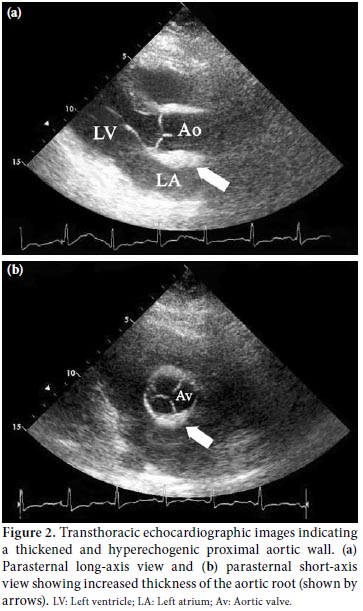

A 48-year-old female patient with no known cardiovascular risk factors was referred to our emergency department due to the sudden onset of severe, constricting chest pain that had been occurring for the previous four hours. On physical examination, blood pressure measurements from the right and left arms were 155/90 and 130/80 mmHg, respectively, and an apical 2/6 systolic heart murmur was heard. Electrocardiography (ECG) showed a 1 mm ST-segment depression in the precordial derivation and a 1.5 mm ST elevation in augmented vector right (aVR) (Figure 1). Laboratory tests revealed a creatinine level of 1.8 mg/dL, a urea level of 80 mg/dL, and slightly increased troponin/creatine kinase-MB fraction (CKMB) levels. Based on the patient's medical history, she had been diagnosed with Takayasu's arteritis 12 years earlier due to renal artery stenosis, subclavian artery stenosis, and intermittent claudication. In addition, a pulmonary embolism had been detected four years previously. Transthoracic echocardiography showed normal left ventricular systolic function, mild aortic regurgitation, and moderate tricuspid regurgitation. The systolic pulmonary artery pressure was 35 mmHg. The ascending aorta was measured as 4.0 cm, and no dissection flap was detected. An echocardiographic examination revealed that the proximal aorta was thickened and hyperechogenic, and calcific plaques were commonly observed on the inner surface of the lumen (Figure 2). Using suprasternal imaging, it was determined that the arcus aorta was 4.3 cm in width, and moderate proximal brachiocephalic, common carotid, and subclavian artery stenoses were detected. Thickening of the arcus aorta wall was observed in addition to an increased echogenic area and a rough inner lumen (Figure 3). Due to ongoing severe chest pain, the patient was urgently transferred to the catheter laboratory. Spontaneous dissection causing severe stenosis in the proximal left main coronary artery (LMCA) was detected by coronary angiography (Figure 4), but all other coronary vessels were normal. In addition, there was no significant narrowing observed on the carotid Doppler ultrasound. The patient's hemodynamic values were normal, and an emergency operation was planned. Ascending aorta, upper, and lower vena cava cannulations were performed after a median sternotomy and then the patient entered into the pump. The heart was stopped by cold potassium while the patient was under general (rectal temperature 28 °C) and topical hypothermia. During an intraoperative evaluation of the thoracic aorta, it was noted that it was completely calcified and hardened. Aortocoronary anastomosis was performed using a saphenous venous graft because of the ostial involvement of the subclavian and left internal mammary arteries (LIMA). The postoperative course was uneventful, and the patient was discharged on postoperative day 10.